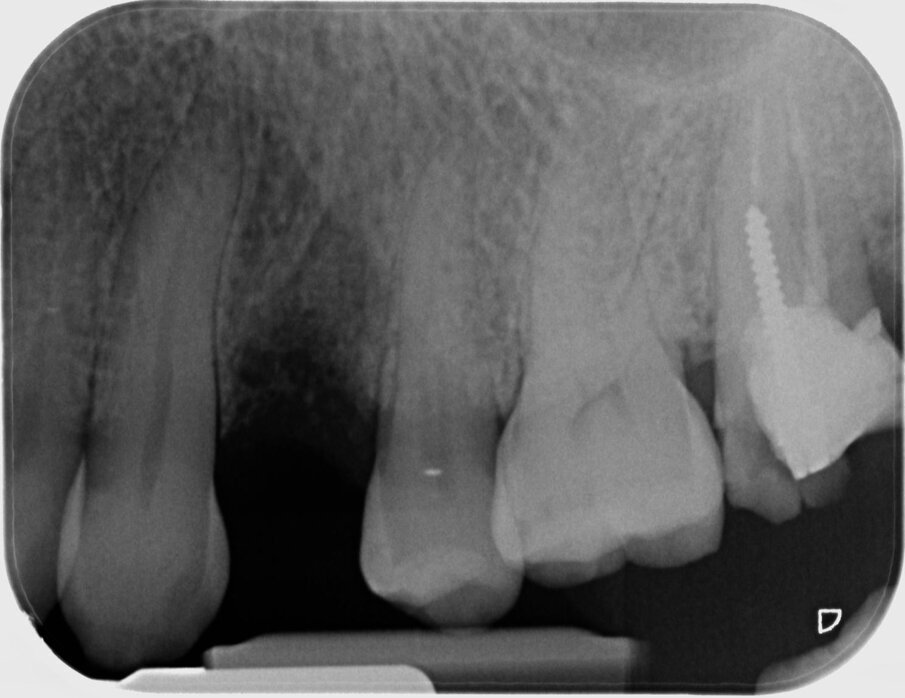

Fig. 7 - Radiografia postoperatoria che mostra il biomateriale in situ.